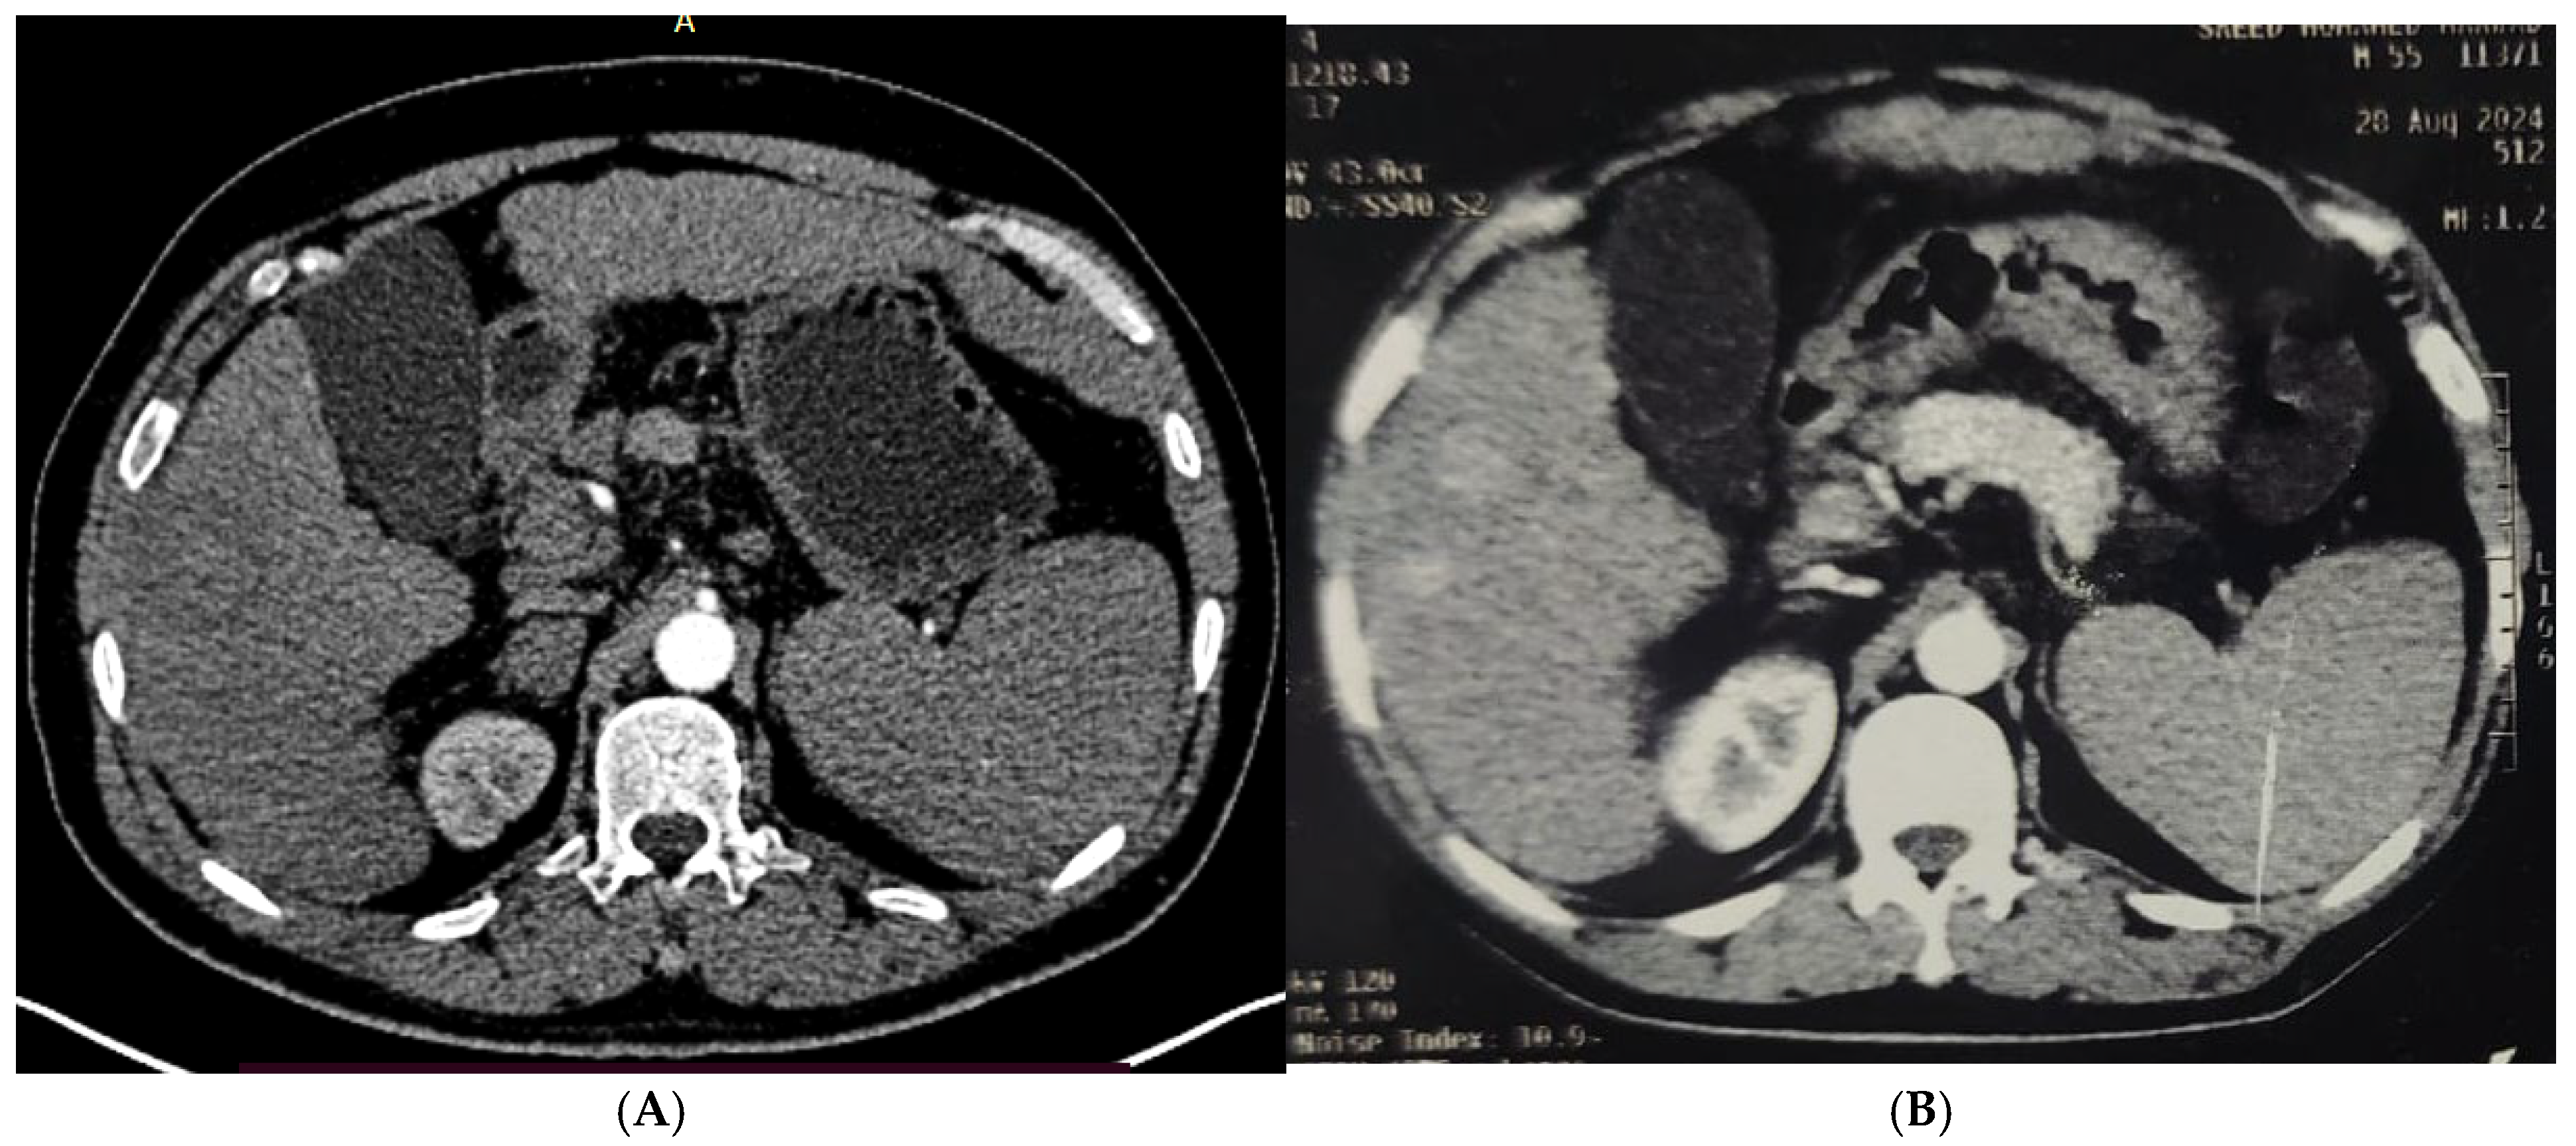

2.2.2. Procedures